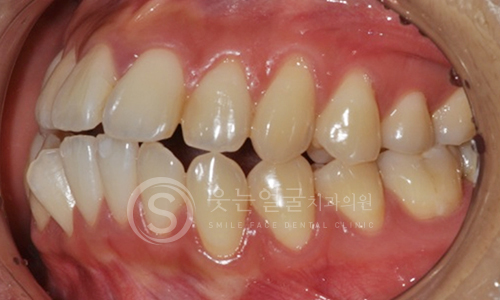

한눈에 보는

임플란트 전후사진